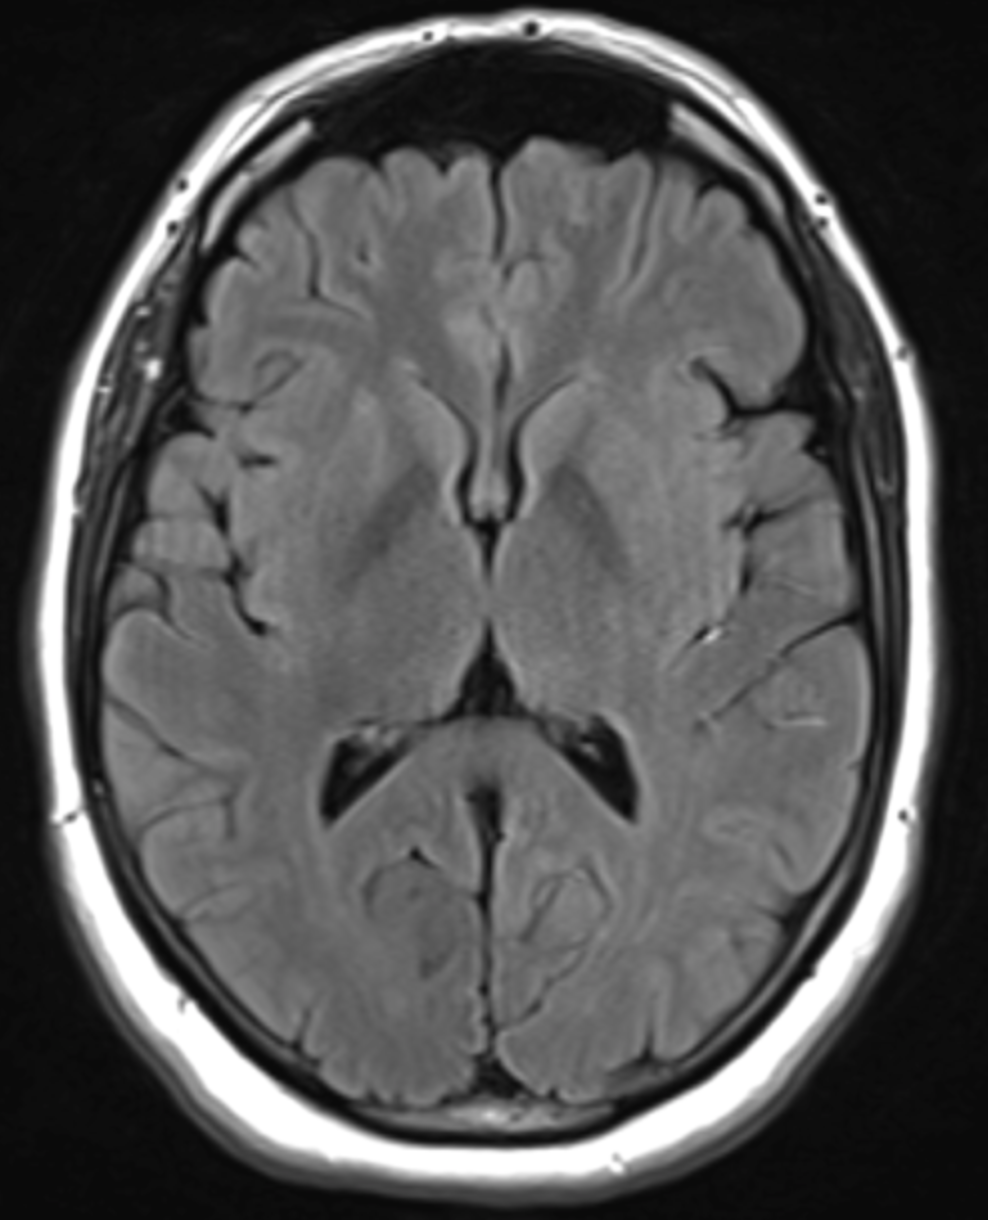

Quelle est la séquence de cet IRM ?

T2 Flair